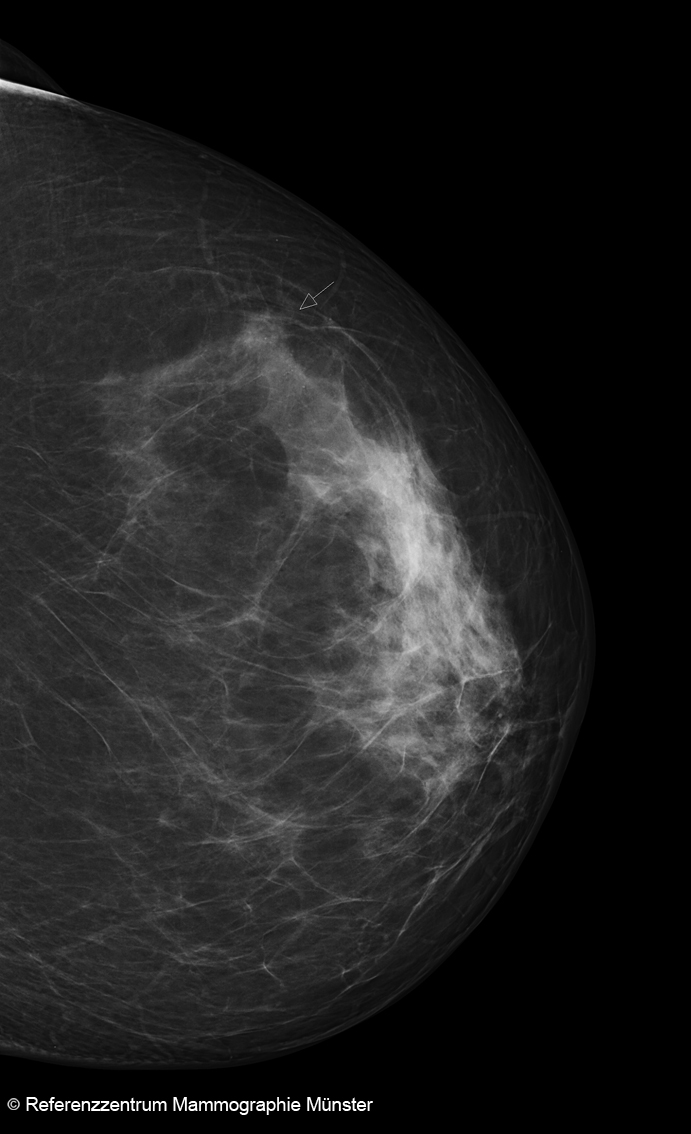

Mammographie-Screening: Niedrigere 2-Jahresinzidenz fortgeschrittener Tumorstadien in Folgerunde

Die Inzidenz fortgeschrittener Brustkrebsstadien ist ein wichtiger Surrogatparameter für die zu erwartende Brustkrebsmortalität. Eine neue Studie aus Nordrhein-Westfalen zeigt im Sinne des „Proof of Principle“ anhand der 2-Jahresinzidenzen auf, dass durch wiederholte Teilnahme am Mammographie-Screening UICC II- bis IV-Stadien einschließlich von Intervallkarzinomen seltener auftreten als bei Erstuntersuchungen.